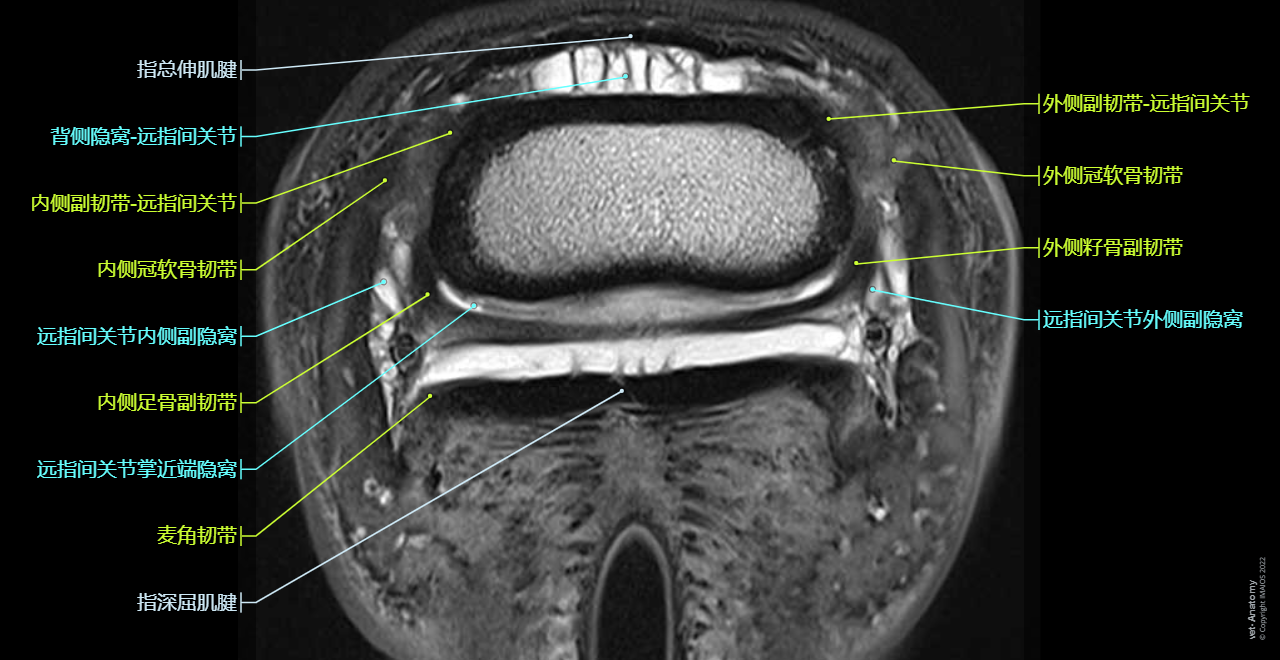

Cross-sectional labeled anatomy of the equine digit on MR imaging (hoof, foot, phalanges (long pastern bone, short pastern bone, coffin bone, distal sesamoid bone), sesamoid ligaments, Superficial digital flexor tendon (SDFT), Deep digital flexor tendon (DDFT), Common digital extensor tendon, podotrochlear bursa, proper digital artery, vein an nerve, hoof capsule)

Cross